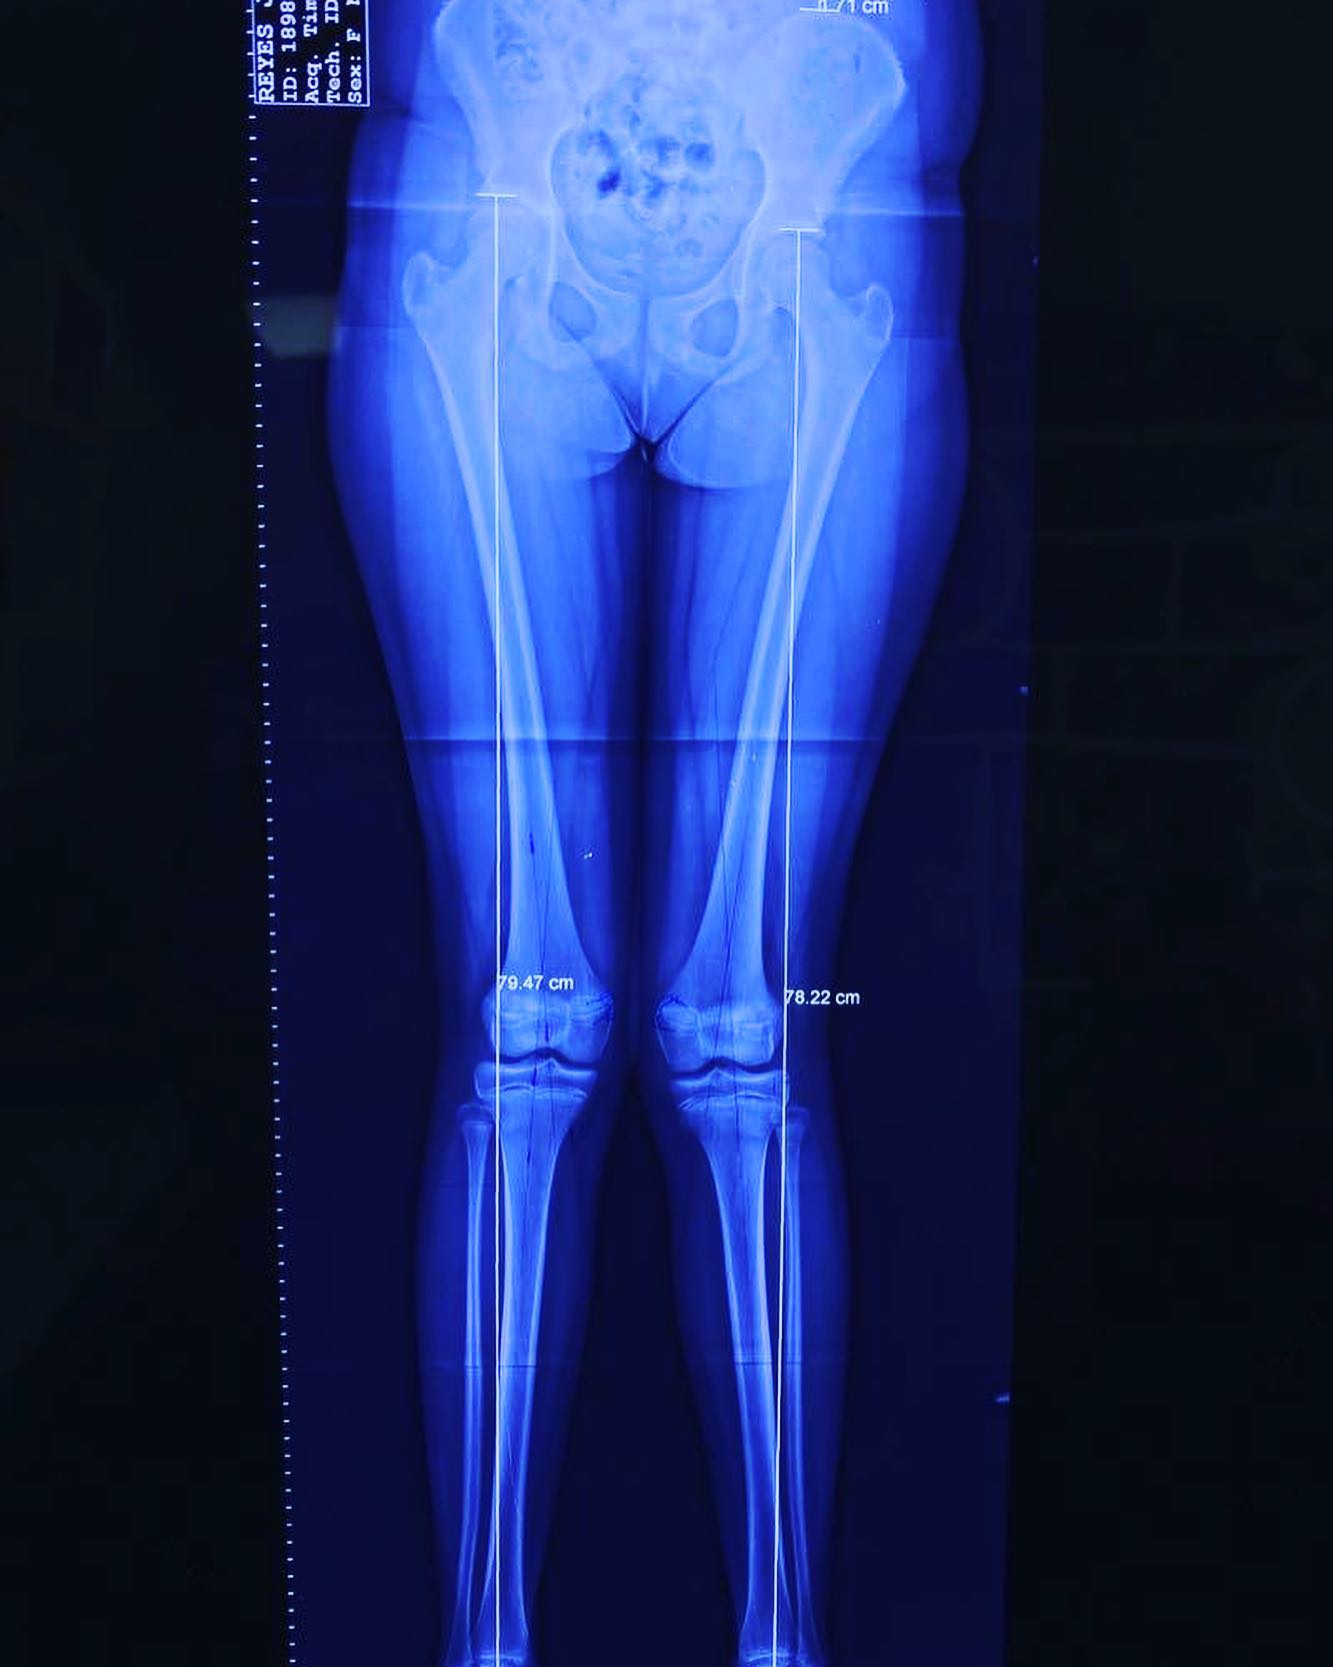

deformidad rodillas en valgo

Ella es mi pacientita Danna, de 13 años. Vino a consulta por una deformidad muy común: “rodillas en valgo”. Por suerte, llegó a tiempo y logramos corregirla al 💯. ¡Felicidades, Danna! Ahora sí, ¡a darle al gym! 💪 💪🏻